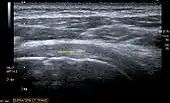

Transversal ultra sonography of the supraspinatus tendon

Ultrasound

There are several advantages of ultrasound. It is relatively cheap, does not emit any radiation, is accessible, is capable of visualizing tissue function in real time, and allows the performance of provocative maneuvers in order to replicate the patient’s pain.[26] Those benefits have helped ultrasound become a common initial choice for assessing tendons and soft tissues. Limitations include, for example, the high degree of operator dependence and the inability to define pathologies in bones. One also has to have an extensive anatomical knowledge of the examined region and keep an open mind to normal variations and artifacts created during the scan.[27]

After the introduction of high-frequency transducers in the mid-1980s, ultrasound has become a conventional tool for taking accurate and precise images of the shoulder to support diagnosis.[29][30][31][32][33]

Adequate for the examination are high-resolution, high-frequency transducers with a transmission frequency of 5, 7.5, and 10 MHz. To improve the focus on structures close to the skin an additional "water start-up length" is advisable. During the examination the patient is asked to be seated, the affected arm is then adducted and the elbow is bent to 90 degrees. Slow and cautious passive lateral and/or medial rotations have the effect of being able to visualize different sections of the shoulder. In order to also demonstrate those parts which are hidden under the acromion in the neutral position, a maximum medial rotation with hyperextension behind the back is required.[34]